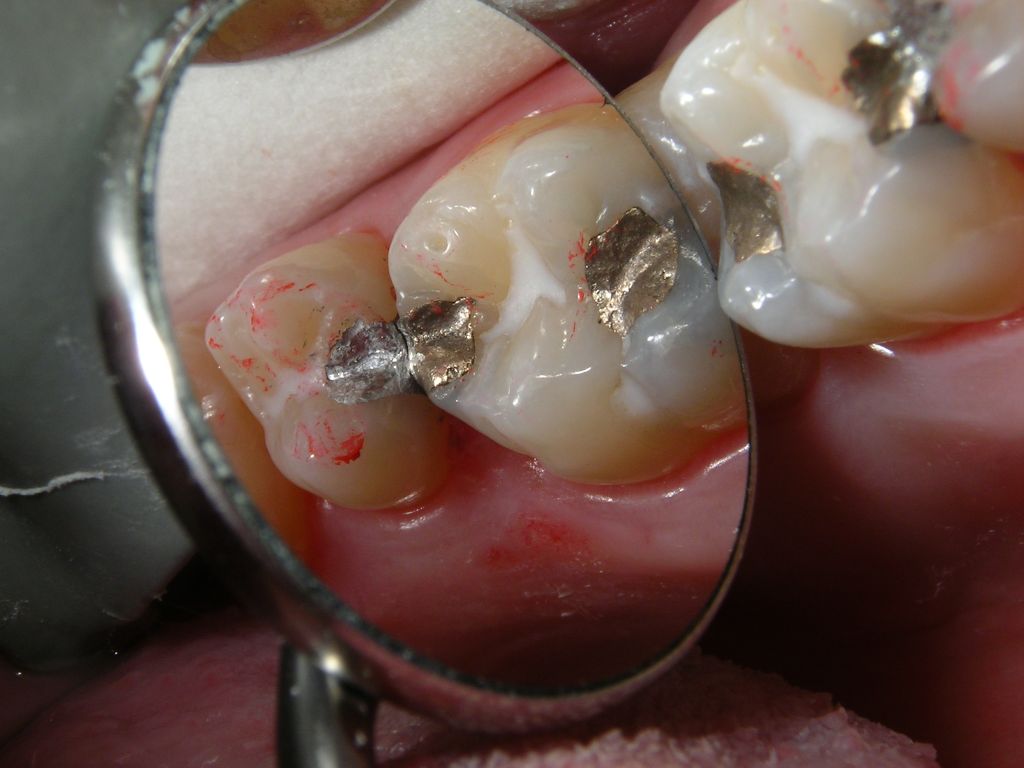

Frisch gelegte u. brünierte Amalgamfüllung

Im Frontzahnbereich sind die weißen Kompositfüllungen natürlich das Mittel der Wahl. Auch kleine Füllungen, inbesondere in den vorderen, besonders sichtbaren, kleinen Backenzähnen, lassen sich mit Composite gut versorgen. Generell gilt: Je größer die Füllung, desto größer wird der Haltbarkeitsvorsprung für Amalgam. Die ästhetische und über Jahrzehnte haltbare Alternative zu großen Amalgamfüllungen sind deshalb nicht große Kunststofffüllungen, sondern keramisch verblendete Kronen, die problemlos auf die mit Amalgam sanierten Backenzähne zementiert werden können: